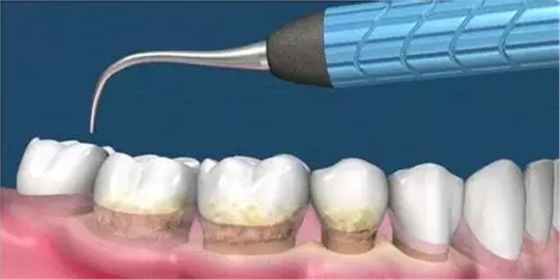

這是牙周病常規(guī)的治療方法,清除或控制臨床炎癥和致病因素,去除病因,消除炎癥。包括口腔衛(wèi)生宣教、充填齲洞、口腔潔治刮治、牙體牙髓治療、咬合調(diào)整、去除不良修復(fù)體、藥物治療(輔助手段,局部用藥效果好)、拔除治療效果不佳的牙周病患牙等。